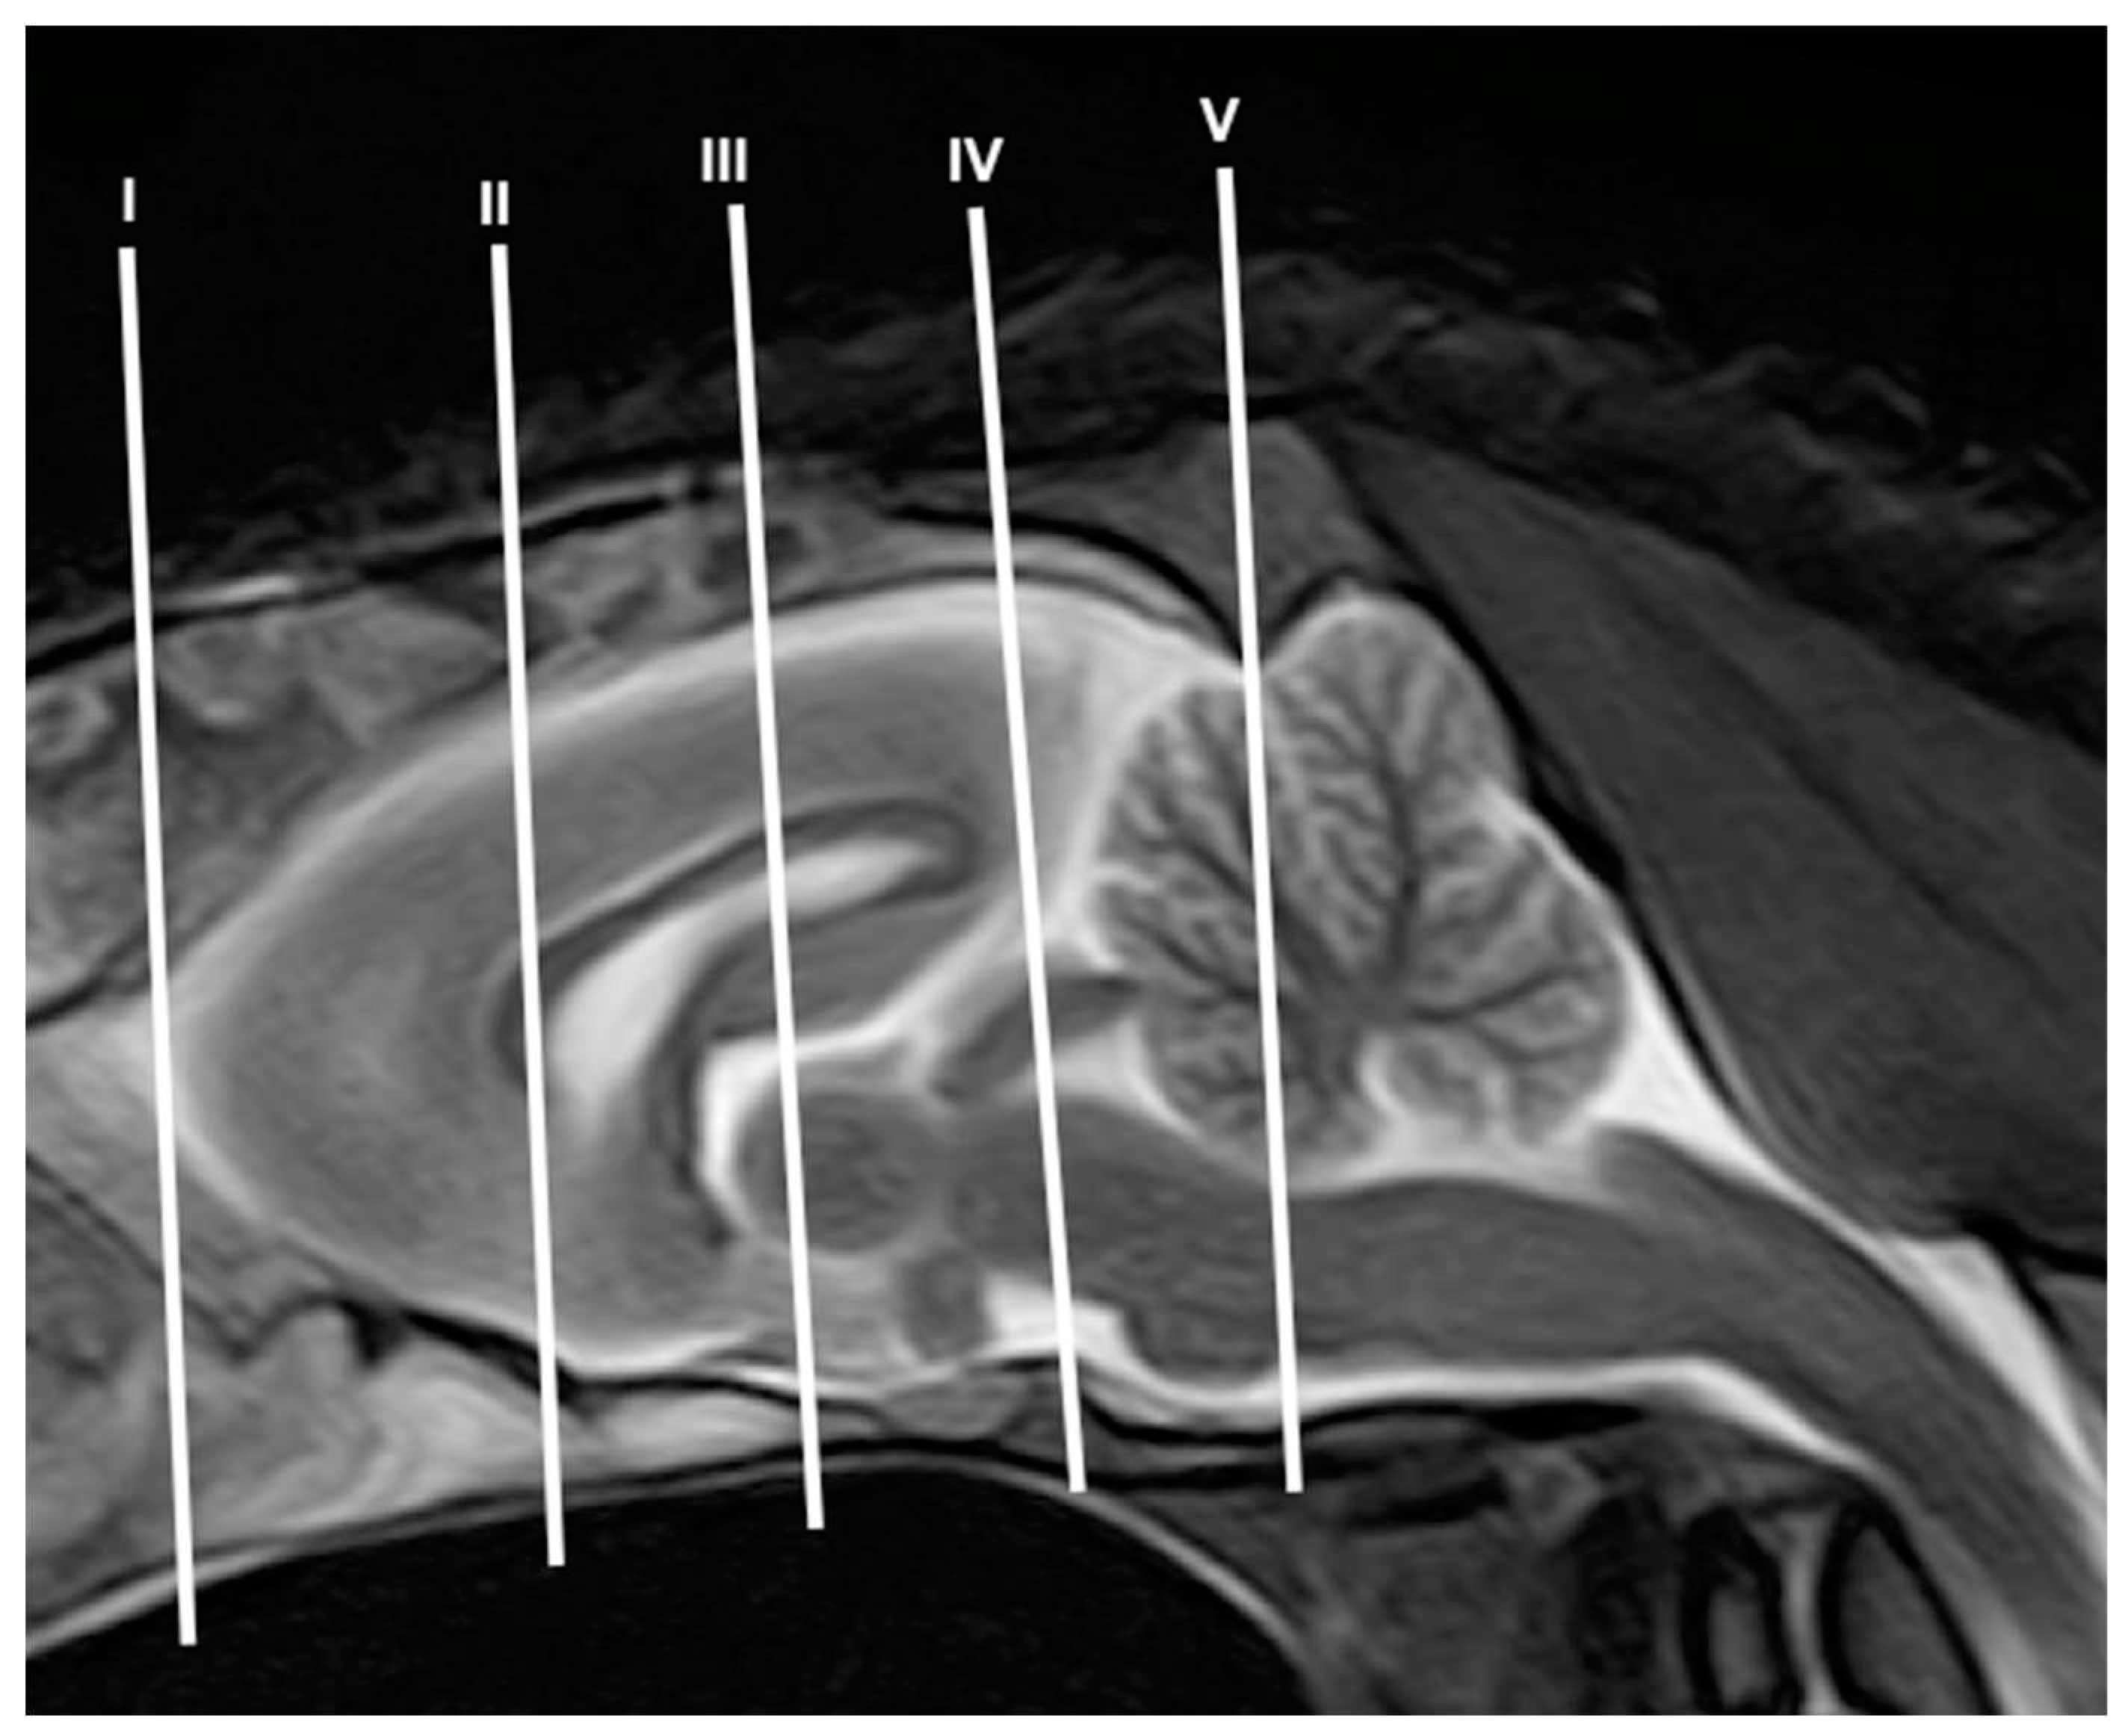

3.1. Anatomical gross-sections

3.2. Magnetic Resonance Imaging (MRI)